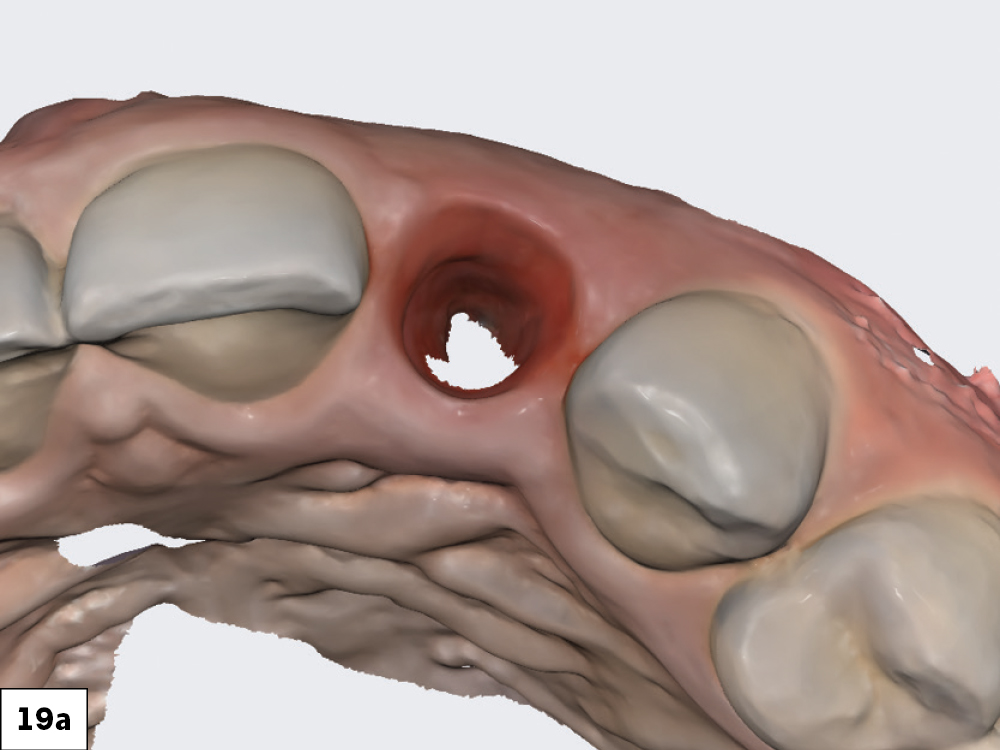

The scan body was then registered with the IOS. With the soft tissue previously scanned and locked in place, there was no concern about the soft tissue collapsing while the scan body was being radiographed and its position captured.

Figures 19a, 19b: The scan body was then registered with the IOS. With the soft tissue previously scanned and locked in place, there was no concern about the soft tissue collapsing while the scan body was being radiographed and its position captured.